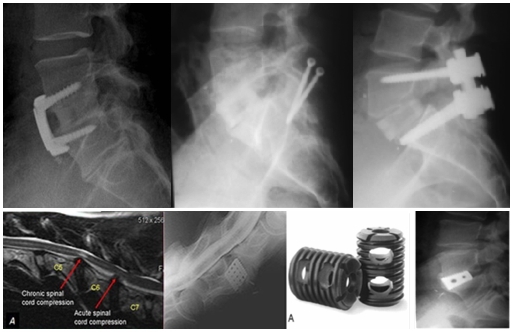

作为腰椎前路手术发展的里程碑,内固定的应用和椎间融合器的出现开创了ALIF技术的新局面。1961年,Humphries首次在ALIF使用前路内固定。随着后路内固定的出现,人们开始使用联合前-后路融合术,大大增加了ALIF手术的融合率和可靠性[7]。而椎间融合器最初是用于治疗马Wobbler综合征。1992年,改进为钛金属的BAKcage首次用于人体,很大程度上解决了取骨区疼痛、感染、骨量不足的问题[8]。

笔者及团队自1998年起开展了腹腔镜下腰椎融合技术,该技术可以说是现代OLIF技术的全内镜下的“版本”。然而,在临床应用过程中,腹腔镜锁孔下操作存在着上述诸多问题,为兼顾微创的同时改善手术的便利性与实用性,2002年起,腰椎前路融合手术均革新为腹腔镜辅助小切口或单纯小切口方式进行。在融合器稳定性方面,由于早期缺乏自稳装置,前路术后往往需要进行后路补充固定。近年来,随着理念的进步和经验积累,涌现了附有自身稳定的融合器如LDR等。为此,结合自锁cage的应用,于2015年设计了腹前外侧入路腰椎间融合(ALLIF)技术,该入路设计简单、直接、安全。术中患者采用斜卧位,切口根据椎间隙的体表投影,贴腹直肌左外缘作4-6cm横/斜切口所经层次:腹外斜肌-腹内斜肌-腹横肌至腹膜外间隙,用常规腹部拉钩将血管及腹膜稍牵向内侧,另一拉钩置于椎体侧前、交感神经链前方,将其稍向后牵开。辅以头灯放大镜或显微镜,直接对神经结构进行减压,选用自锁型融合器,不需附加前路钉板或后路钉棒,同时对于退行性滑脱的病例,采用前侧入路方式可以获得有效的椎体复位,从而达到减压、复位、融合与稳定等“四位一体”,“一箭多雕”之目的[16,17]。